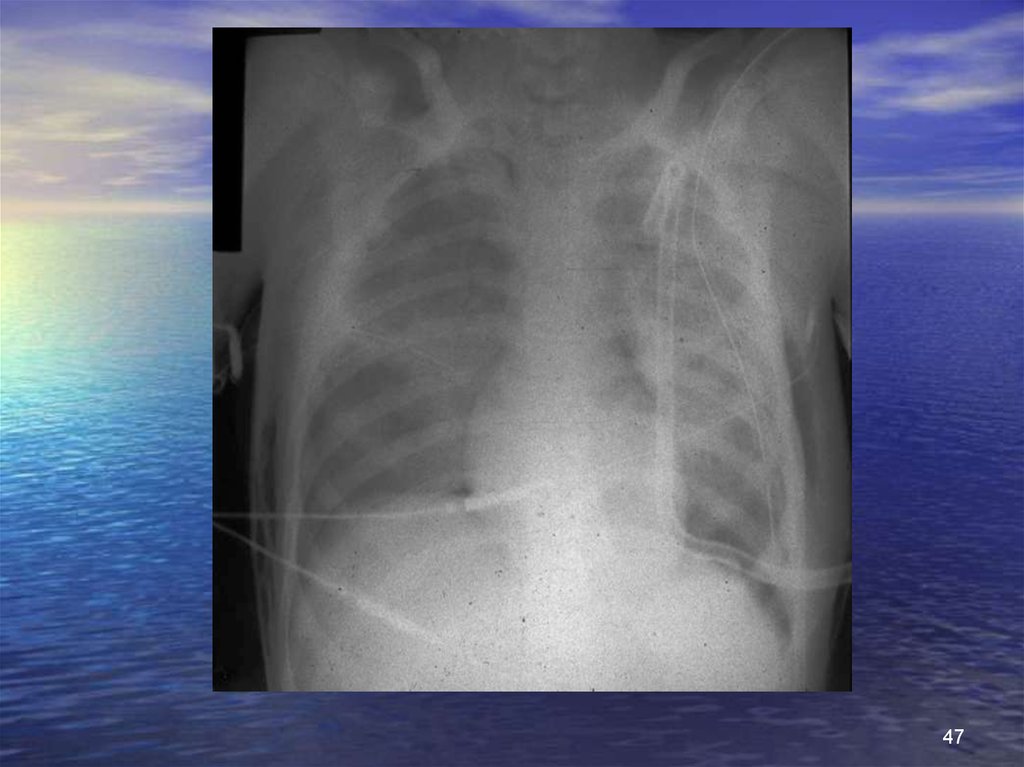

47.

47